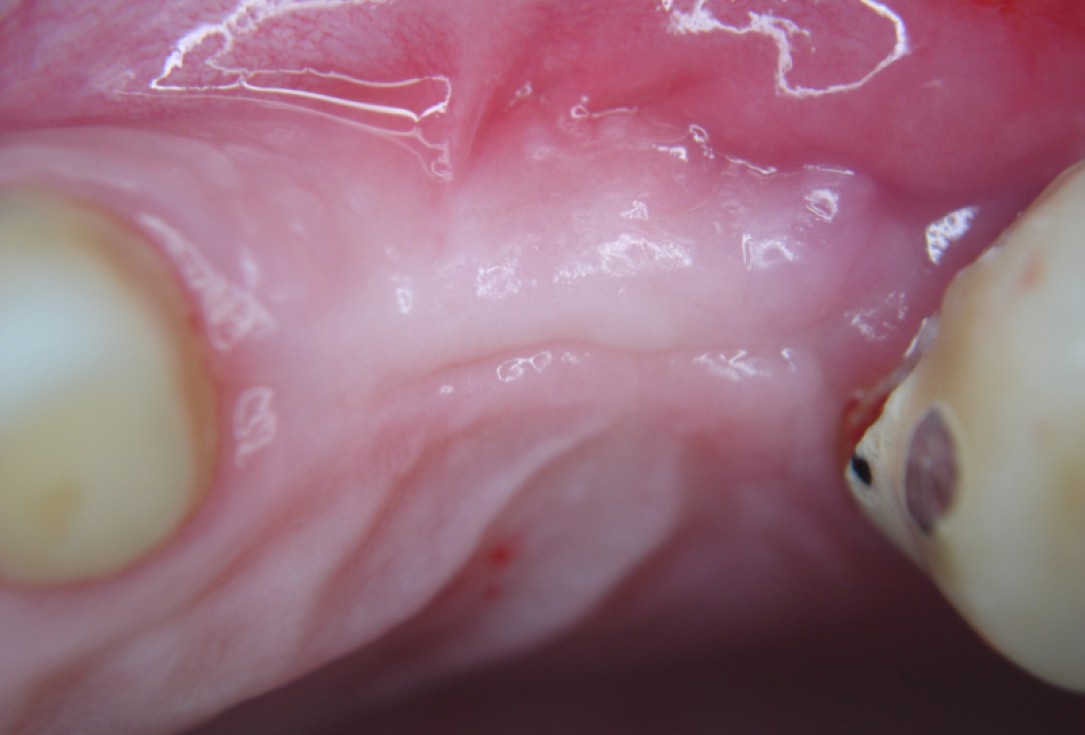

Initial clinical situation with gum recession and labial bone loss eight weeks following tooth extraction